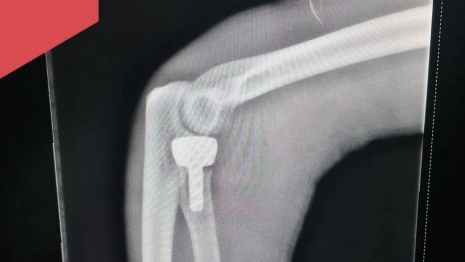

Врачи предложили пациенту современный, органосберегающий метод – эндопротезирование головки лучевой кости.

Операция длилась около часа. Молодому человеку установили эндопротез из керамики.